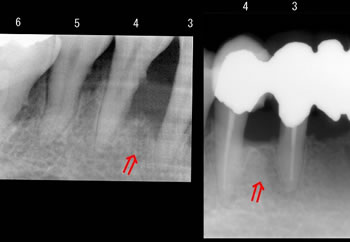

お口の中の同じ部位で「左が初診時」で「右が再生治療後」のレントゲンです! |

赤い矢印の部分が歯槽骨の再生した場所です。

(3は3番目の歯、4は4番目の歯です) |